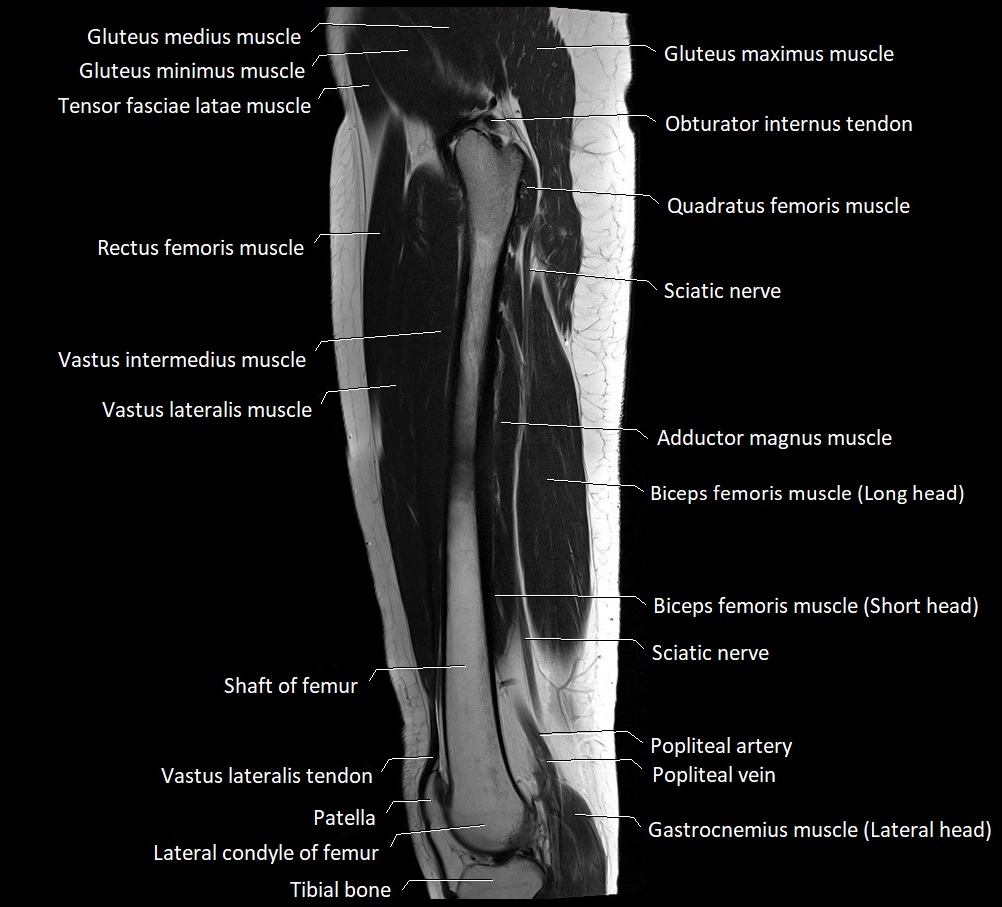

- Biceps femoris muscle (Long head)

- Biceps femoris muscle (Short head)

- Gastrocnemius muscle

- Gluteus maximus muscle

- Gluteus medius muscle

- Gluteus minimus muscle

- Patella

- Quadratus femoris muscle

- Rectus femoris muscle

- Tensor fasciae latae muscle

- Tibial nerve

- Vastus intermedius muscle

- Vastus lateralis muscle